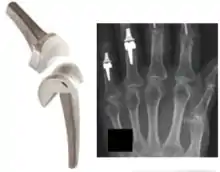

Finger joint replacement.

Finger joint replacement is a relatively quick procedure of about 30 minutes, but requires several months of subsequent therapy.[10] Post-operative therapy may consist of wearing a hand splint or performing exercises to improve function and pain.[11]